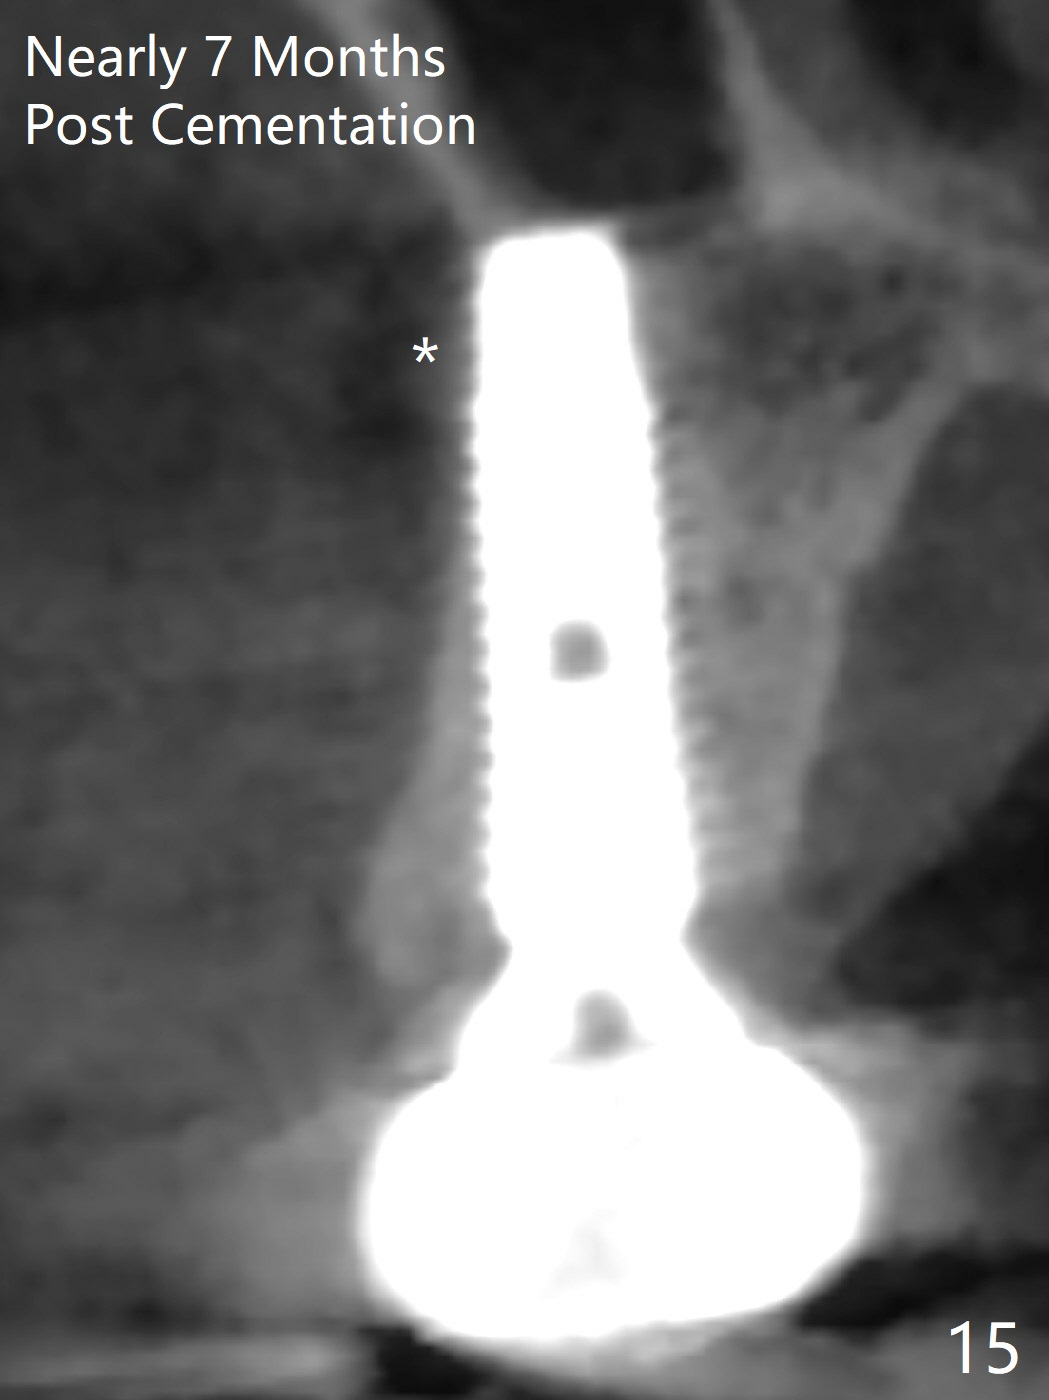

The palatal cusp of the affected 2nd premolar is apparently rotated distal (Fig.1). It is more obvious for the socket (Fig.2): the palatal (P) portion of the socket is more distal than the buccal (B) one. When the gauze is removed (Fig.3), Lindamann bur is used to remove the disto(D)palatal bone of the socket (data not shown), followed by starter drill in the DP wall obliquely (Fig.3'). Once the drill enters the bone for 1-2 mm, the bur is straightened and pushed slightly distal (Fig.3''). Fig.4 shows a parallel pin distal (overcorrect) to the original socket (Fig.4 red dashed line). Sequential osteotomy is conducted until 3.8x13 mm drill for 18 mm (Fig.5): note the 2 steps of the osteotomy (red lines). Since the apical portion of the osteotomy is larger than the drill, a larger implant than expected (5x16 mm) is placed. The implant ends up in the middle of the edentulous area (due to the stepped osteotomy; Fig.6-9; >60 Ncm). Vera allograft is placed (Fig.7-9 *) prior to and after placement of a 6.5x4(3) mm abutment (Fig.8-10). The remaining socket opening is sealed with a piece of Collagen plug (Fig.10 *). The socket is then closed by an immediate provisional (Fig.11 P). The abutment is retightened 2 months postop (Fig.12,13). The crown is cemented 4.5 months postop. Panoramic X-ray and CT are taken nearly 7 months post cementation (Fig.14,15) when the patient is ready for #30 implant guide preparation.